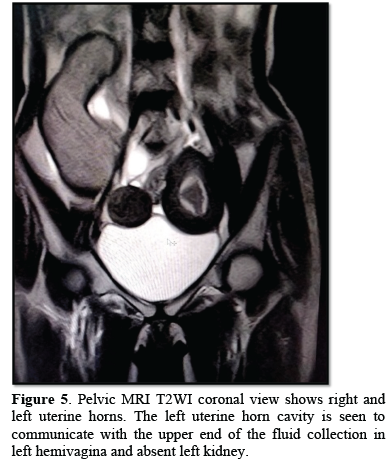

A 17 years old female was admitted in our emergency with acute abdomen complaints. She was unmarried and her previous menstrual cycle was normal. She gave history of amenorrhea for past two months and her UPT was negative. General physical examination was unremarkable. Mild tenderness was noted in lower abdomen without any rigidity or muscle guarding on per abdominal examination. On per vaginum examination, an ill-defined tender, cystic mass was felt in lower abdominal wall with restricted mobility and without cervical motion tenderness. So, possibility of ectopic pregnancy was kept and further investigation was advised. Transabdominal ultrasonography showed separate divergent uterine horns (Figure 4), with left sided hematocolpus (Figure 5) and left renal agenesis suggestive of OHVIRA syndrome. MRI confirmed the diagnosis. Her postoperative period was uneventful. On further follow up she had normal menstrual cycle and on examination there was no evidence of hematocolpus.